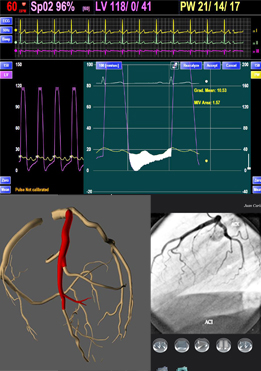

Sistemas de Información Pacs Cardiológico Caracteristicas

Picasso Cathlab Monitoring and information System